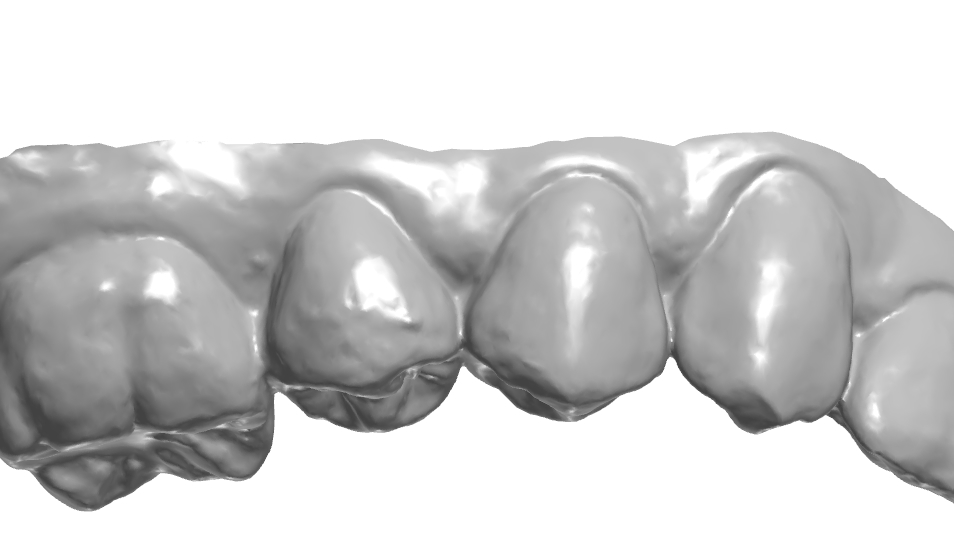

협측에 있는 엠브레져 체크.

치경측에 존재하는 협측, 설측 엠브레져 체크.

치은 라인의 연속성 체크.

협측 풍융도 체크.

치은 라인가 치간 사이 엠브레져 체크.